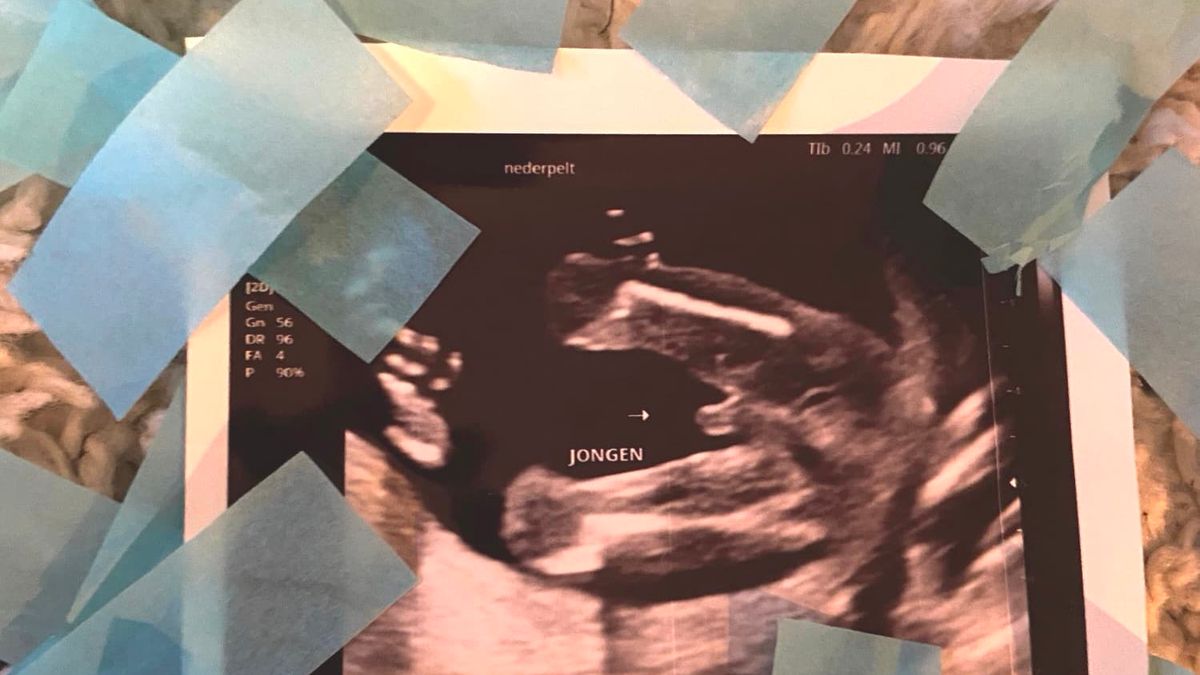

Het geslacht

Dinsdagavond 8 december was de echo bij de verloskundige. Er werd naar het geslacht gekeken. Alles zag er goed uit. Blij en opgelucht. We kregen het geslacht in een enveloppe en de juiste kleur confettikanonnen mee.

Het was Kerstavond. Alle vier stonden we met onze confettikanon klaar. De kamer kleurde met blauwe confetti. “Zie je: een jongen”, dacht ik. Ach en zijn broers waren zo blij. Een broertje, dat hoopten ze zo! Wie had gedacht dat nog geen week later ons leven compleet op zijn kop zou staan. Na een leuke kerst in coronastijl, fantaseerden we over de kerst volgend jaar met de kleine erbij. Ik voelde hem inmiddels ook echt heel goed bewegen. Aan de buitenkant voelde je dit ook. Het heerlijkste gevoel dat er bestaat.